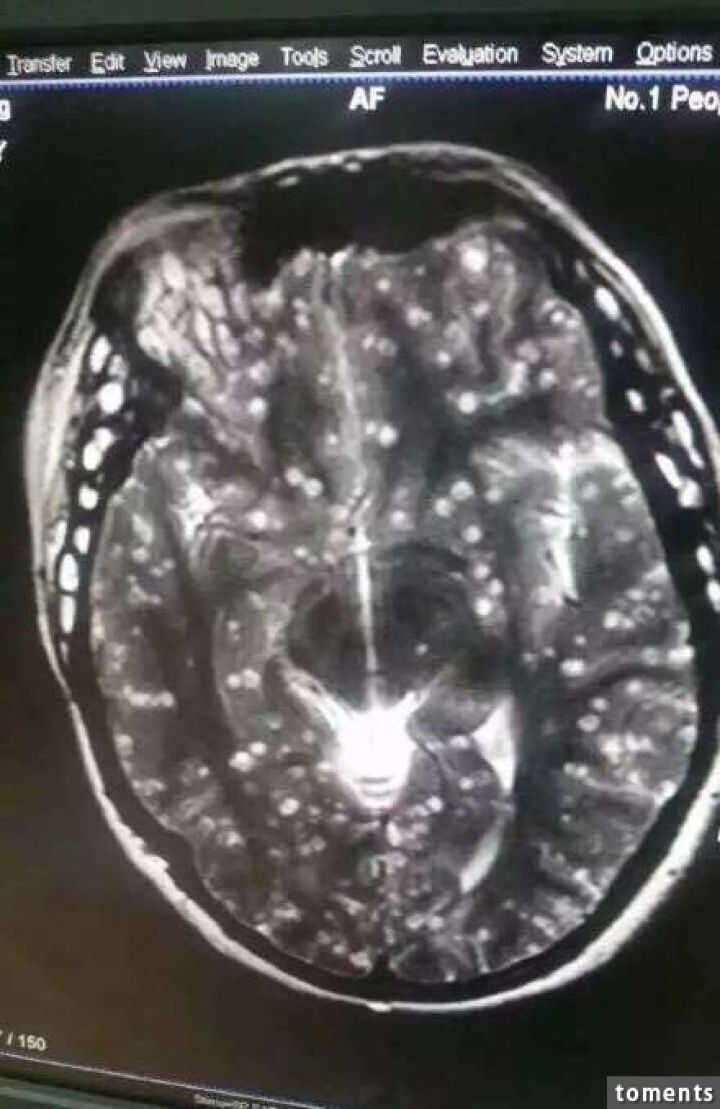

病院では頭部MRIと全身CTスキャンが行われたが、その検査結果は専門家さえも驚く衝撃的なものだった。

それもそのはず、女性の全身はすでに無数の寄生虫に侵されており、大脳や顔面の筋肉にさえも感染が見られるひどい

有様だったからだ。